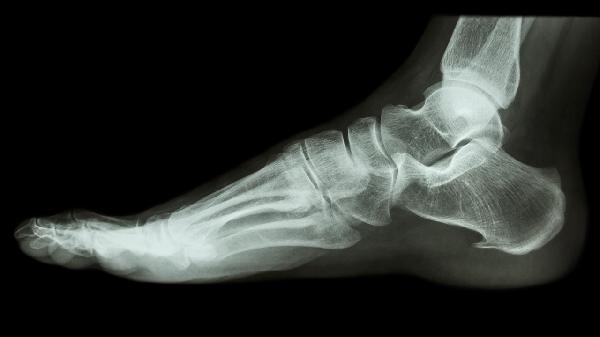

跟骨牵引术如何护理 跟骨牵引术的三个护理技巧分享

跟骨牵引术可通过保持牵引装置稳定、预防感染、观察患肢血液循环等方式护理。跟骨牵引术是治疗骨折或关节脱位的常用方法,需严格遵循医嘱进行术后护理。